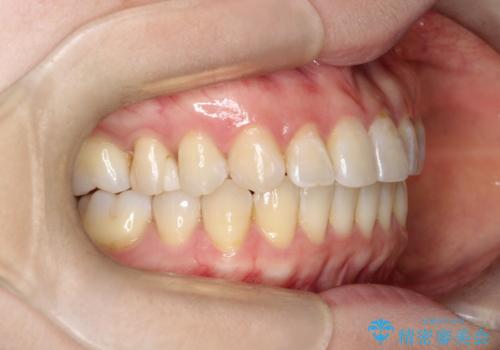

【インビザライン 】前歯の凸凹をなおしたい

- 前歯の凸凹を主訴に来院されました。

インビザライン にて治療を行い、歯並びが綺麗になったと満足していただきました。

前歯のガタガタの量が多かったため、IPR(歯のサイズを小さくするための処置)を行なって治療しました。